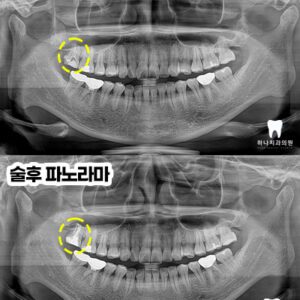

울산삼산동치과 매복된 사랑니 발치와 임플란트 수복(대합치 형태 회복) 안녕하세요! 하나치과입니다~:) 백세 시대라 불리는 요즘, 오복 중 하나로 여겼던 치아의 기능은 삶의 질을 좌우하는 요소가 될 수 있는데요. 현대사회에…